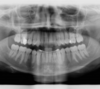

Les radios avant le traitement